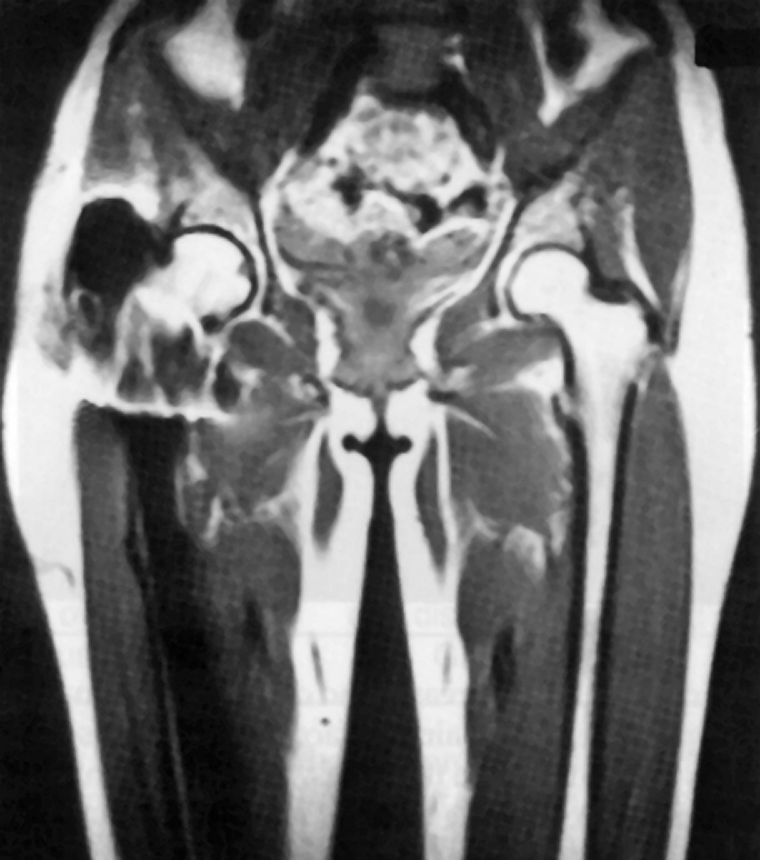

Figura 17-04:

Artifacts resulting from the presence of ferromag­netic material. Signal loss and signal dis­tor­tion as­so­­ci­a­ted with a fer­ro­mag­ne­tic prosthesis in the right leg.